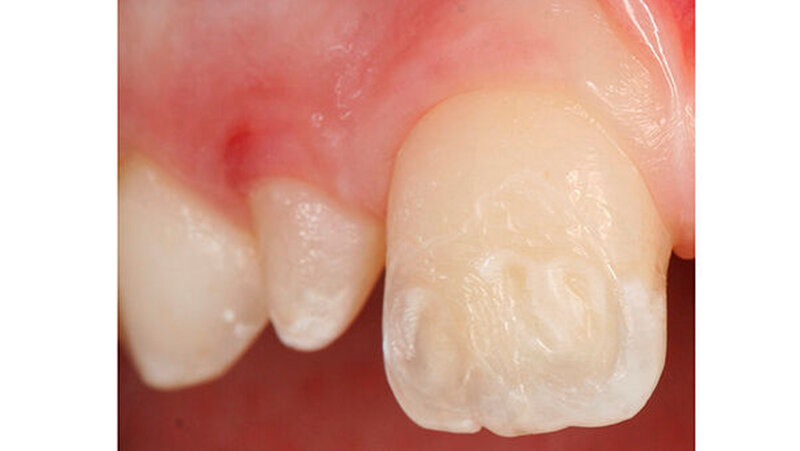

Die Behandlung der MIH stellt an Patienten und Behandler dadurch ganz besondere Herausforderungen, denn zu der Schmerzempfindlichkeit/Überempfindlichkeit der Zähne kommt die in der Regel schlechte Anästhesierbarkeit der betroffenen Zähne hinzu [Steffen & van Waes, 2011]. Die Behandlungsnotwendigkeit im Durchbruch erschwert das Kavitätendesign, die Trockenlegung und die Wahl des Füllungsmaterials erheblich [Lygidakis et al., 2010]. Aber auch nach vollständigem Durchbruch bleibt die Frage des Kavitätendesigns und der erforderlichen Restauration bestehen [Lygidakis et al., 2010].

Wie im Fall zur Füllungstherapie ausführlich beschrieben, ist der Haftverbund der derzeit verfügbaren Materialien aufgrund des hypomineralisierten Schmelzes in der Regel nicht zufriedenstellend und oft von einem frühzeitigen Füllungsverlust und/oder einem weiteren Einbruch in den an die Restauration angrenzenden Bereichen begleitet (Abbildungen 9 und 10).

Je nach Größe des eingebrochenen Defekts werden folgende Optionen – in Abhängigkeit von Alter des Patienten, Lokalisation und Schweregrad der betroffenen Zähne und Anästhesierbarkeit - für den Seitenzahnbereich empfohlen: